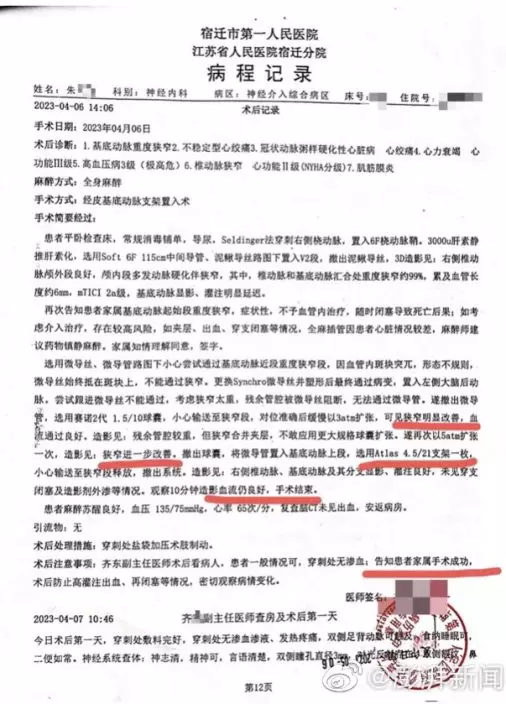

院方手術記錄報稱在向管內釋放支架,手術成功。

病程記錄多次提到向管狹窄情況改善。

當時醫生告知家屬,如果不予血管內介入治療,患者隨時可能因動脈閉塞導致死亡。經家屬簽字同意,4月6日,齊某再次作為主刀醫生,對朱老翁進行經皮基底動脈支架植入術,術後告知家屬手術成功。手術記錄均顯示,朱老翁安裝了一枚進口Neuroform Atlas 4.5/21支架,病程記錄也多次提到「血管狹窄明顯改善」。朱老翁4月10日「康復」出院,家屬結清了住院醫療費用,合計12萬餘元,部分自費。收據顯示,其中顱內支持導管收費1.88萬,神經導絲4275元,而Neuroform Atlas進口顱內支架為4.7萬元。